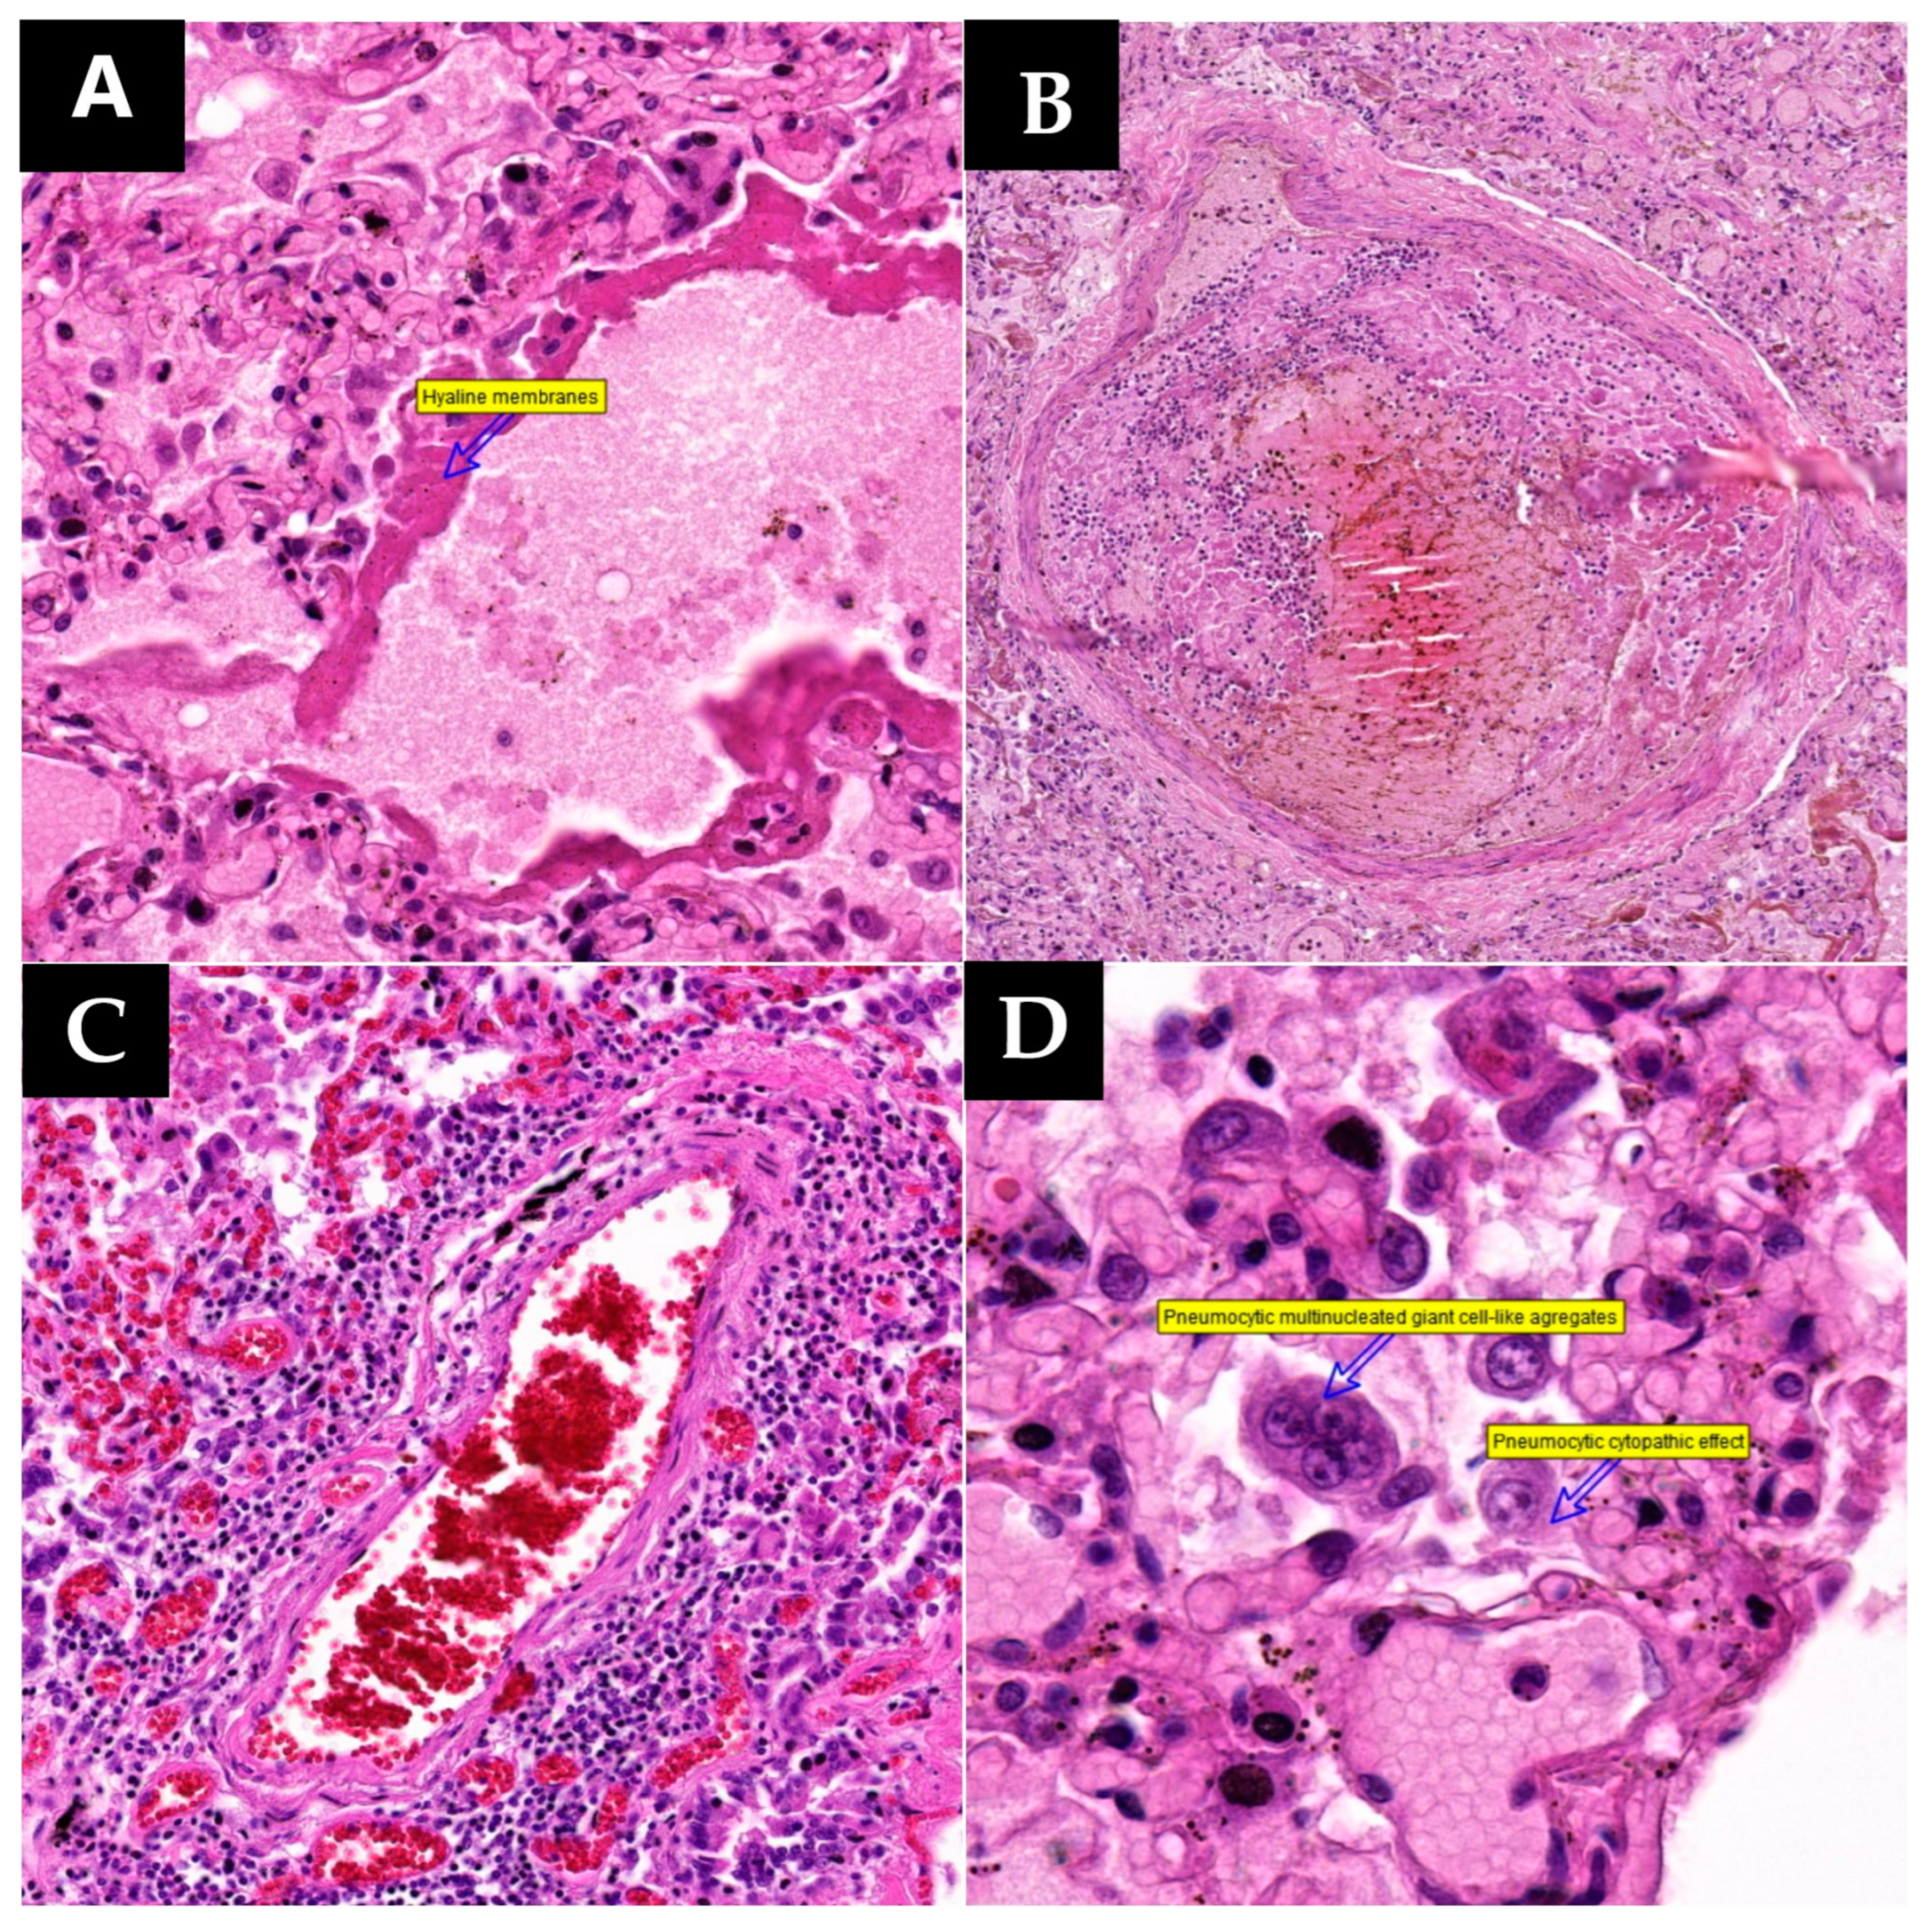

After all autopsies were performed, every sample collected was subjected to histopathology using the classic hematoxylin–eosin stain, immunohistochemical analysis using SARS-CoV-2 nucleocapsid antibody, and rt-qPCR molecular analysis for the detection of the S, N, and ORF1ab genes. We found the most significant changes in the pulmonary tract and, as such, the histopathology of lung tissue sampled from every case revealed the following (

Figure 1):

Acute inflammatory lesions:

- ○

Lympho-monocytic inflammatory infiltrate: 10 cases;

- ○

Polymorphonuclear (mostly neutrophils) inflammatory infiltrate: 9 cases;

- ○

Mixed inflammatory infiltrate: 4 cases;

- ○

Presence of macrophages in the alveolar space: 9 cases.

Acute alveolar lesions

- ○

Hyaline membrane formation: 9 cases;

- ○

Type II pneumocyte hyperplasia: 13 cases;

- ○

Pneumocytes with cytopathic effect: 10 cases;

- ○

Multinucleated giant cell-like pneumocyte aggregates: 6 cases;

- ○

Megakaryocyte hyperplasia: 2 cases.

Vascular lesions

- ○

Vasculitic reaction: 3 cases;

- ○

Microthrombosis: 5 cases.

Hemodynamic injuries

- ○

Pulmonary edema: 7 cases;

- ○

Diffuse alveolar hemorrhage: 8 cases.

Interstitial and aberrant regenerative alterations

- ○

Organizing pneumonia: 4 cases;

- ○

Interstitial fibrosis: 8 cases;

- ○

Squamous metaplasia: 5 cases.

Associated chronic injury

- ○

Chronic passive congestion of the lung: 2 cases;

- ○

COPD (Chronic obstructive pulmonary disease) changes: 3 cases;

- ○

Vascular changes secondary to pulmonary hypertension: 2 cases;

- ○

Neoplasm: 1 case.

The majority of cases of inflammatory infiltrate were attributed to the presence of lymphomonocytic infiltrate, observed in 10 cases. This infiltrate exhibited either a focal disposition, with areas of lymphocytes or monocytes alternating with non-inflamed areas, or a diffuse disposition, involving the entire analyzed parenchyma to varying extents. Both focal and diffuse forms were near equally represented in the study group; the first was found in five cases and the second observed in six cases. Afterwards, the inflammatory infiltrate was subdivided into either a rich infiltrate or a poor inflammatory process. Infiltrate classification as rich or reduced was based on inflammatory cell digital quantification, where a rich infiltrate constituted over 50% of the histological structure. Five cases showed a rich lymphomonocytic infiltrate with a focal disposition, while four cases exhibited a rich infiltrate with a diffuse disposition. Cases with a mildly augmented lymphomonocytic infiltrate were fewer, with only two cases in focal disposition. The focal infiltrate was more perivascular, peribronchial, interalveolar, interlobular, or subpleural, while the diffuse infiltrate extended widely through the lung parenchyma. Most of the lymphocytes expressed CD3 positivity. Among the 15 patients, 9 of them exhibited a more predominantly neutrophilic polymorphonuclear infiltrate. Quantitatively, there was a relatively equal distribution among subcategories, with two cases having a rich focal polymorphonuclear infiltrate, four cases having a reduced focal infiltrate, and three cases showing a rich diffuse polymorphonuclear infiltrate. Unlike the lymphocytic infiltrate, the polymorphonuclear infiltrate was predominantly alveolar but also involved interalveolar septa, interlobular septa, and perivascular areas. Another category of inflammatory lesions involved acute phase macrophages in alveolar spaces, observed in nine patients. This was confirmed by CD68 immunostaining.

In specimens collected from 13 patients, histopathological examination revealed changes secondary to alveolar lesions, with the most common being type II pneumocyte hyperplasia. Among patients with suggestive histopathological changes in type II pneumocyte hyperplasia, 10 exhibited variable proportions of hyperplastic pneumocytes with cytopathic effects (

Figure 2). Cytopathic effects result from the invasion of a cell, typically by a cytopathic virus, leading to morphological, physiological, biological, and genetic alterations. Virally infected cells undergo shape and size changes, dysfunction of the cytoskeleton, and secondary nuclear changes and often display cytoplasmic or nuclear inclusions formed by newly formed virions or their structural proteins [

16].

In six collected specimens showing pneumocyte hyperplasia with viral cytopathic effects, altered cells occasionally fused to form syncytia, referred to as pneumocytic aggregates with giant cell-like formation or syncytial giant cell-like aggregates (

Figure 2). These can be easily mistaken for multinucleated giant cells of histiocytic origin. This was confirmed by CF7 and TTF1 positive immunostaining and CD68 negative immunostaining. Syncytium formation involves cell-to-cell fusion and is commonly observed in infectious processes. The ability of viruses to mediate membrane fusion for host cell invasion is employed for transmembrane transfer between infected donor cells and neighboring uninfected cells, facilitating local–regional expansion and potentially contributing to syncytium formation. The formation of syncytia is primarily mediated by specific interactions between viral fusion proteins and surface molecules or receptors expressed on adjacent uninfected cells [

17]. Giant-like cells in autopsy specimens exhibit wide aggregates with eosinophilic cytoplasm, abundant large nuclei, round-oval, irregular, homogeneous chromatin, predominantly peripheral nuclear disposition, visible nucleoli, disordered nuclear arrangement without a specific pattern, and occasional discernible boundaries between fused cells.

Another significant histopathological change within the spectrum of diffuse alveolar lesions is the formation of hyaline membranes, observed in nine cases. These membranes consist of dense, intensely eosinophilic, acellular bands on the inner surface of alveolar walls, composed of pneumocytic debris and fibrin (

Figure 2).

Addressing acute changes, vascular lesions, including microthromboses and vasculitic reaction, were observed in the current cases. Microthromboses, extensively discussed in the literature, underscore the need for anticoagulant treatment in severe COVID-19 pneumonia. Hence, this study emphasized the inclusion of tissue specimens from diverse pulmonary areas for effective vascular evaluation, covering broad lung fields. Vascular thrombi, of either small or large caliber, were observed in five cases (

Figure 2). In contrast, vasculitic reaction was noted in only three patients. Histologically, the vasculitic reaction did not manifest as classic leukocytoclastic vasculitis with secondary fibrinoid necrosis. Instead, it exhibited a lymphocytic nature, with lymphocytic groups penetrating the vascular wall from the adventitia toward the vascular endothelium (

Figure 2). Among these patients, only one presented both types of vascular lesions.

Histopathological examination revealed a series of hemodynamic changes, primarily characterized by pulmonary edema and diffuse alveolar hemorrhage. Accordingly, seven cases exhibited pulmonary edema, while eight cases showed diffuse alveolar hemorrhage. Among these, five patients presented both pulmonary edema and diffuse alveolar hemorrhage, and ten patients exhibited at least one form of these two conditions.